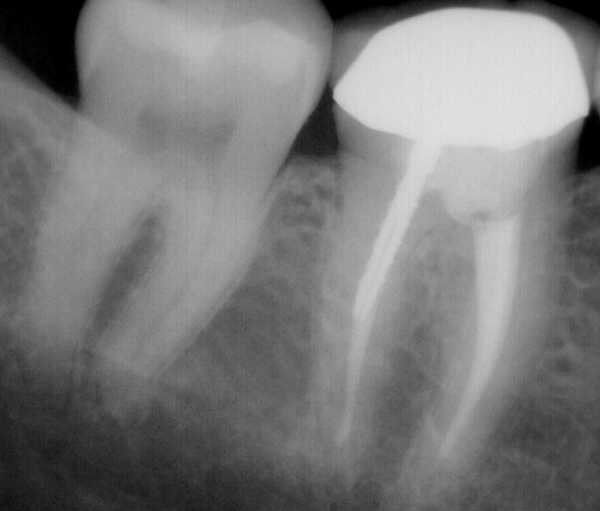

Modern tools like digital X-rays and rotary endodontic files improve accuracy and reduce the risk of missed canals or reinfection.